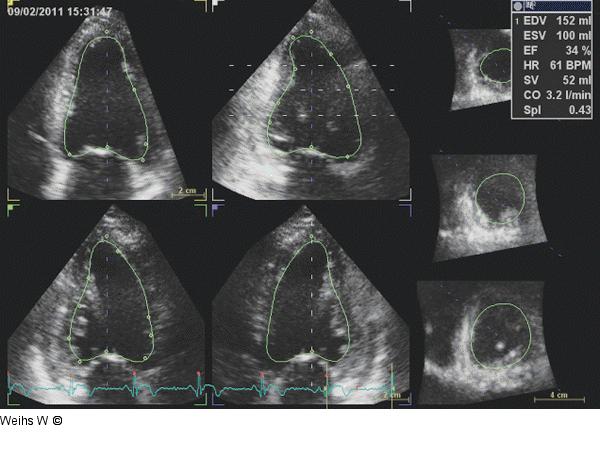

Abbildung 7: Linksventrikuläre Volumina - EF Automatisierte Messung der linksventrikulären Volumina und EF in einer dreidimensionalen Aufzeichnung des linken Ventrikels. Weitere mögliche Parameter sind der "sphericity index", die linksventrikuläre Masse sowie Strain-Analysen. |

Automatisierte Messung der linksventrikulären Volumina und EF in einer dreidimensionalen Aufzeichnung des linken Ventrikels. Weitere mögliche Parameter sind der "sphericity index", die linksventrikuläre Masse sowie Strain-Analysen. |